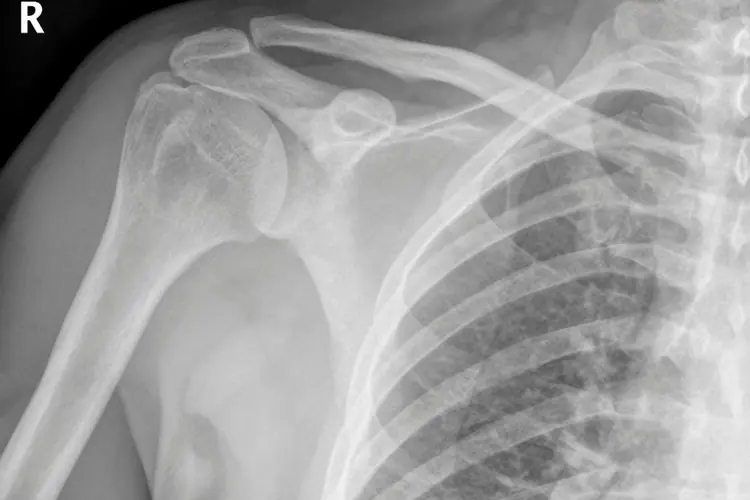

Fratture

Cos'è una Frattura: Una frattura è una rottura o una frattura in un osso. Le fratture sono comunemente il risultato di traumi o stress e possono variare notevolmente in termini di gravità, dalla frattura più semplice o "chiusa" in cui l'osso è rotto ma la pelle è intatta, a fratture aperte in cui l'osso perfora la pelle. Le fratture possono verificarsi in qualsiasi parte del corpo e richiedono una valutazione medica per determinare la gravità e il trattamento appropriato.